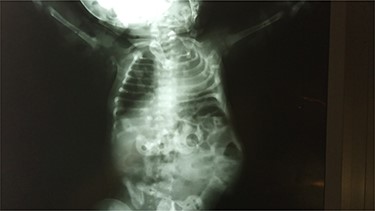

Abdominal X-ray revealed absence of the left 10th to 12th ribs along with half of the 9th rib and a mild lumbar scoliosis (Fig. 2). The shadow of the intestines was seen close to the left abdominal wall. Lateral abdominal X-ray showed a defective ninth hemivertebra (Fig. 3). Abdominal sonography showed absence of muscles of the lateral abdominal wall in the left lumbar region and a lumbar hernia with a diameter of 2.5 cm. Liver, spleen and both kidneys were normal. Laboratorial tests did not raise any suspicions.